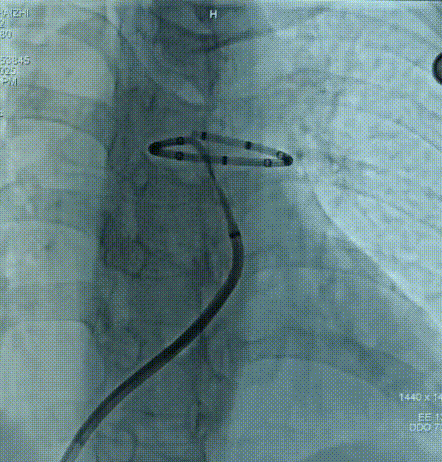

导管出鞘

通道建立后,进入消融导管,调整合适位置后进行消融。

首次消融位置